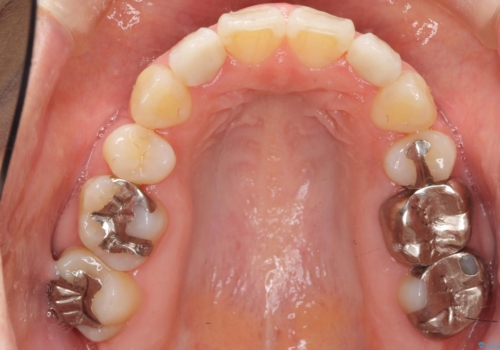

矯正治療後、矮小歯をセラミッククラウンにより理想的な歯の大きさに仕上げました。

自然な仕上がりにご満足頂けました。

「自分でもどこを治したのかわからないくらい自然!」と喜んで下さいました。

クラウンの種類:オールセラミッククラウン スペシャル